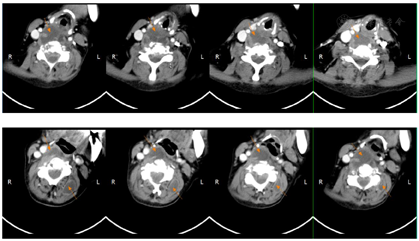

2018年7月2日患者第二次我院住院诊治,此时患者仍有发热,伴额头、左颈部,胸壁多处等多部位脓肿形成,胸部CT、颈部CT、头颅MR、腹部MR较前均有进展,多部位脓肿形成(图1,图2,图3,图4),入院后予B超引导下胸壁脓肿穿刺引流(图5),穿出脓液60 ml左右,穿刺液涂片抗酸阳性,穿刺液培养提示:非结核分枝杆菌生长,菌种鉴定提示疑似胞内分枝杆菌,患者既往血培养鉴定提升哥伦比亚分枝杆菌,考虑患者为播散性哥伦比亚分枝杆菌病,根据MIC结果予调整方案为AmRClrMfxE抗分枝杆菌治疗,后因耳鸣停Am,因药物热不能排除停用R,后调整方案为ClrMfxELzd+替加环素抗分枝杆菌感染,地塞米松减轻炎性反应,治疗后患者体温恢复正常,予出院回当地继续ClrMfxELzd+多西环素抗分枝杆菌治疗。

哥伦比亚分枝杆菌感染临床表现一般无特异性,一般以感染最常见感染部位为肺部,此外还发生于淋巴结、骨、皮肤、胃肠道等部位[2]。哥伦比亚分枝杆菌病肺部受累的影像学表现报道也较少,多无特异性,胸部CT可表现多种征象,如结节、实变、支气管扩张、磨玻璃密度影、纤维索条影、多发空洞、纵隔淋巴结肿大等[3,4]。哥伦比亚分枝杆菌病淋巴结病变表现为淋巴结肿大,CT增强扫描可表现为环状强化[5],骨关节受累可表现为多发溶骨性骨质破坏[6],本例表现播散性感染,肺部表现为双肺粟粒样改变,伴结节条索影,治疗后期出现两侧胸腔积液,纵隔多发淋巴结增大,环形强化不明显。本病例以骨骼侵犯起病,颅骨、颈椎、胸椎、腰椎、肋骨、髋关节,股骨均发生破坏,以侵蚀性溶骨改变为主,伴骨破坏处脓肿形成。